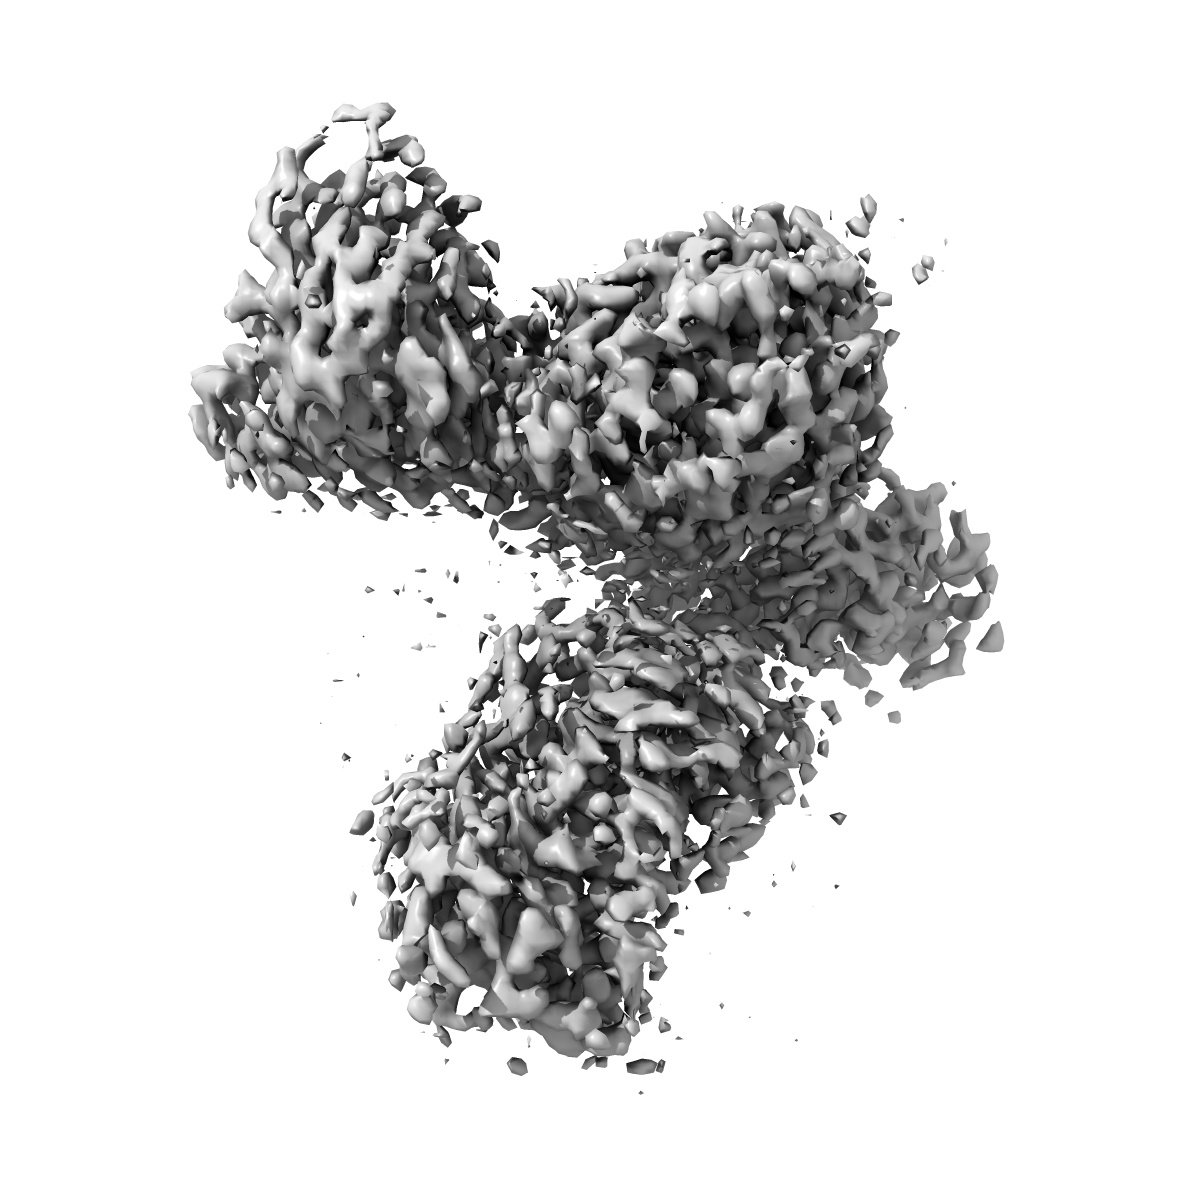

Cryo-EM structure of human galanin receptor 2

Single-particle3.11 Å

Sample: Human galanin receptor 2 complex with Gq heterotrimer

Structure of the human galanin receptor 2 bound to galanin and Gq reveals the basis of ligand specificity and how binding affects the G-protein interface.